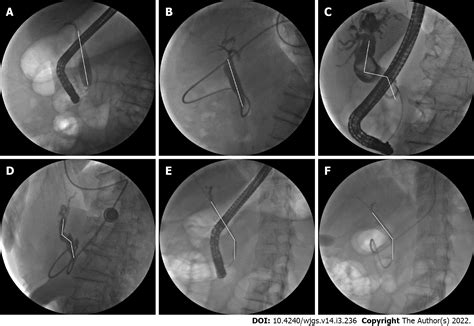

Once bile duct stones are confirmed, the primary goal is to clear the obstruction. The gold standard for treatment is a procedure called Endoscopic Retrograde Cholangiopancreatography (ERCP). During an ERCP, a flexible tube with a camera (endoscope) is passed down the throat into the stomach and the beginning of the small intestine. The doctor can then locate the bile duct, use specialized tools to widen the opening, and retrieve or crush the stone, allowing the bile to flow freely again.